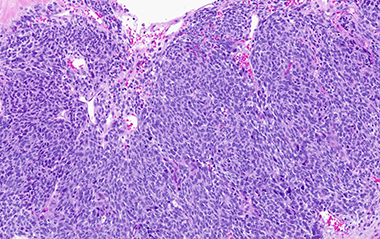

C. Pheochromocytoma with "zellballen" features

D. Pheochromocytoma

Pheochromocytoma was identified comprising 50% of tumor volume. In addition, the lesion contained a primitive round cell component possibly neuroblastoma with focal neuroblastic differentiation (20%) and a malignant peripheral nerve sheath tumor (30%) with heterologous elements (cartilage). Areas of hemorrhage and necrosis were noted resulting in cystic degeneration.

Microscopically, transition between the tumors may be blended or abrupt, pheochromocytoma is almost mostly the predominant pattern with apparent zellballen or variant patterns, GN contains ganglion cells in background of Schwann cells, GNB will have immature and maturing neurons, neuropil and Schwann cells, NB will have small round blue cells and MPNST will show malignant spindle cells with high mitotic count. Note that to designate as composite, although there is no precise portion of the components specified as a definition, there must be complete tumor patterns and not just scattered neurons. Overall, patterns of growth, intermixed cellular components, and immunohistochemistry usually allow this tumors separation from its differential diagnoses.